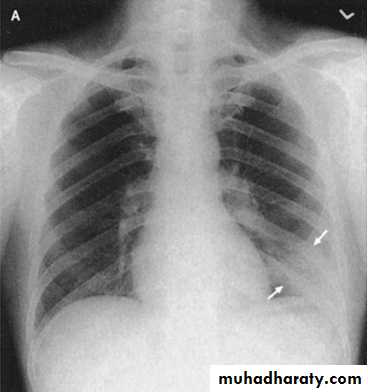

Lobar pneumonia

PA chest x-ray shows consolidation in the left lung base. A lateral view was obtained and shows that the consolidation is located posteriorly. Lateral view are especially important in showing infiltrates, which may be obscured by the heart on PA view.